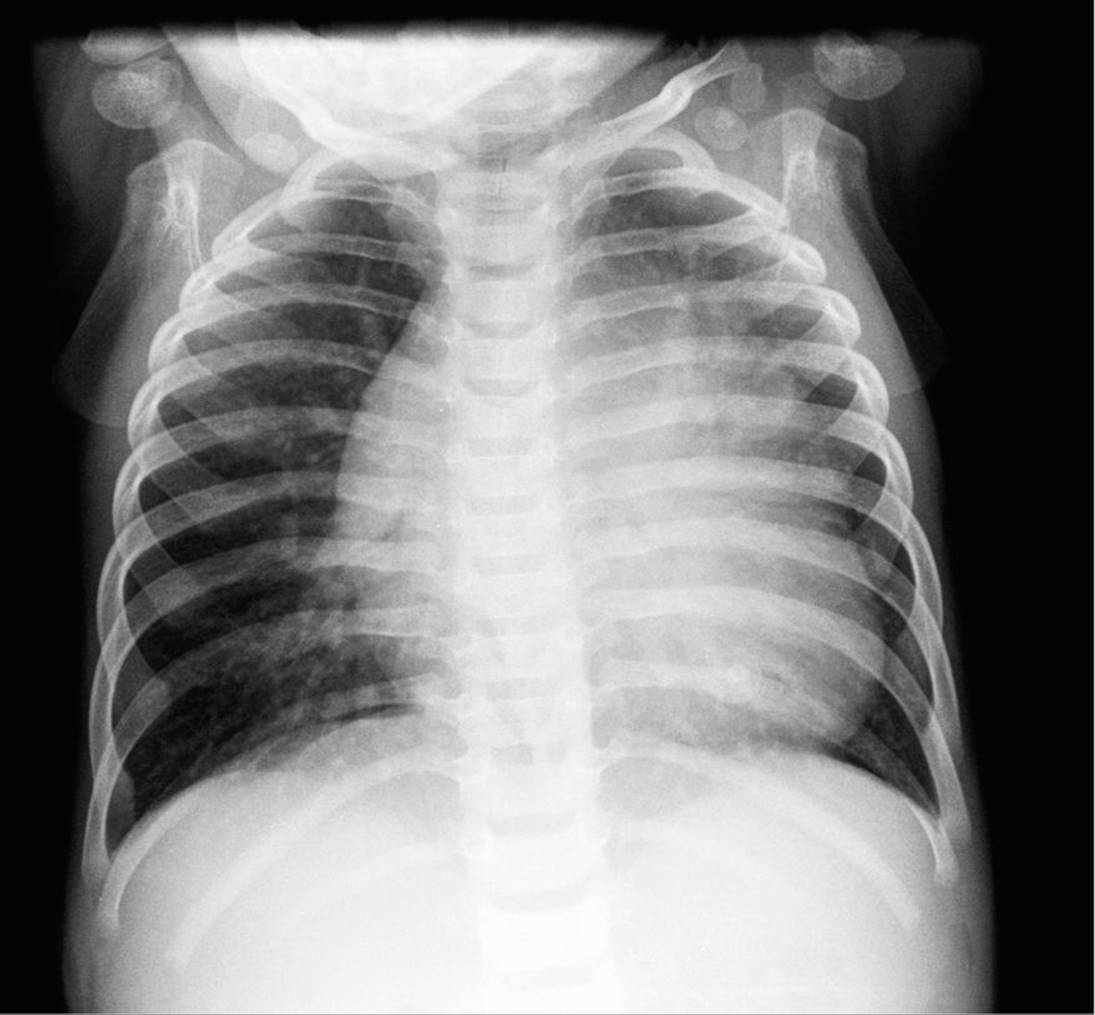

A chest roentgenogram suggested the diagnosis (Figure 14-8).

FIGURE 14-8. Chest radiograph revealing cardiomegaly and pulmonary edema.

The boy’s chest roentgenogram revealed pulmonary edema with massive cardiomegaly (Figure 14-8). An echocardiogram was performed and demonstrated a shortening fraction of less than 20% with left-ventricular end diastolic pressure of 6.4 cm. The left ventricle was noted to be dilated. The diagnosis is a dilated cardiomyopathy. He was initially treated with intravenous furosimide. He was then started on a milrinone infusion. Multiple laboratory studies were sent including infectious serologies and thyroid function tests which did not reveal an etiology for his cardiomyopathy. Ultimately, a cardiac catheterization was performed which revealed a cardiac index of 2.81 and superior vena cava saturation of 75%. An endomyocardial biopsy was performed which demonstrated an eosinophilic and monocytic infiltrate.

Chest roentgenogram. Patients will generally have an increased heart size noted. This is secondary to left-sided dilation. Accompanying signs include pulmonary edema and possibly pleural effusions.